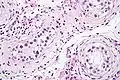

| Intratubular germ cell neoplasia. H&E stain. | |

GCNIS is not palpable, and not visible on macroscopic examination of testicular tissue. Microscopic examination of affected testicular tissue most commonly shows germ cells with enlarged hyperchromatic nuclei with prominent nucleoli and clear cytoplasm. These cells are typically arranged along the basement membrane of the tubule, and mitotic figures are frequently seen. The sertoli cells are pushed toward the lumen by the neoplastic germ cells, and spermatogenesis is almost always absent in the affected tubules. Pagetoid spread of GCNIS into the rete testis is common. Immunostaining with placental alkaline phosphatase (PLAP) highlights GCNIS cell membranes in 95 percent of cases. OCT3/4 is a sensitive and specific nuclear stain of GCNIS.[3]